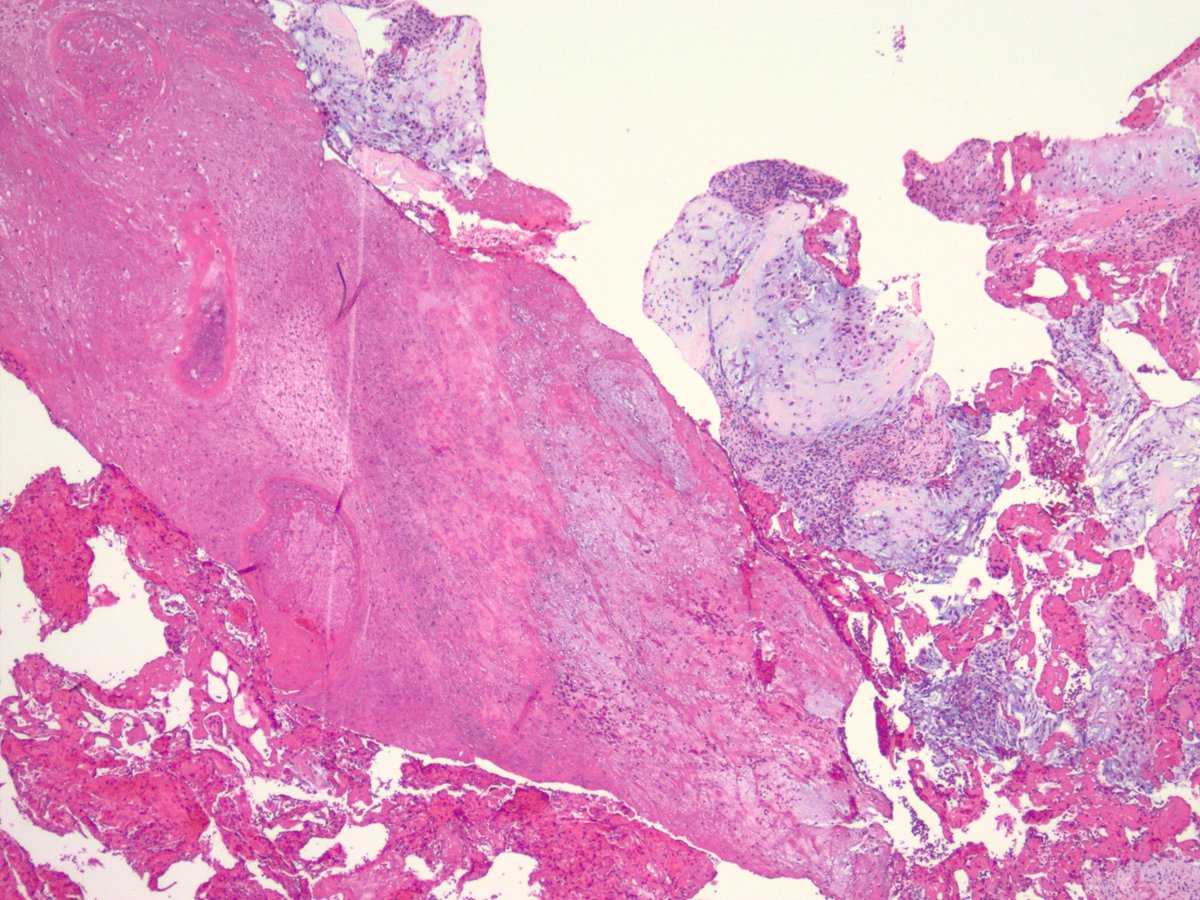

Nasopharyngeal CA (Pics: HP, LP, p40, and EBV ISH).  These can be very tricky as the tumor can be very subtle! Noteworthy feature in this case was the presence of concomitant granulomatous reaction (see PMID 1717637 and 32562216) #PathTwitter #pathology